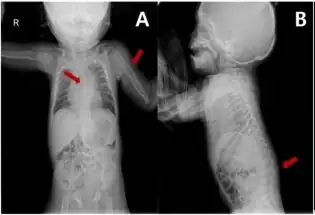

Melnick–Needles syndrome (MNS), also known as Melnick–Needles osteodysplasty, is an extremely rare congenital disorder that affects primarily bone development. Patients with Melnick–Needles syndrome have typical faces (exophthalmos, full cheeks, micrognathia and malalignment of teeth), flaring of the metaphyses of long bones, s-like curvature of bones of legs, irregular constrictions in the ribs, and sclerosis of base of skull.[1]

Skeletal

Individuals with Melnick-Needles typically have a small rib cage and narrow shoulders. The ribs themselves are "ribbon" like and the clavicles are unusually short. The lower portion of the chest appears hollow. Spinal abnormalities may also occur (pectus excavatum).[6] Kyphoscoliosis is common.[7]

S-like curvature of the leg bones is another feature of Melnick-Needles syndrome.[1] The connection between the femur and hip bone may be misaligned, causing an unusual gait. The ilium can be flared and the unusually shape of the pelvis in patients with Melnick-Needles syndrome can make childbirth difficult for affected females.[8]